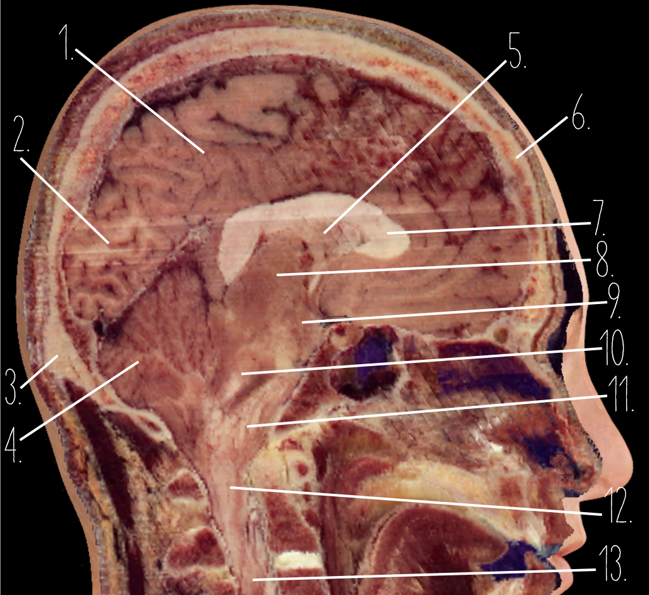

Brain Cross Sectional

127 Terms

1

Frontal Bone

2

Frontal Lobe

3?

Falx Cerebri

4?

Gray Matter

5?

White Matter

6?

Sulcus

7?

Gyrus

8?

Fissure

1?

Parietal Lobe

2?

Cerebellum

3?

Occipital Bone

4?

Cerebellum

5?

Lateral Ventricle

6?

Frontal Bone

7?

Corpus Callosum

8?

Thalamus

9?

Hypothalamus

10?

Midbrain

11?

Pons

12?

Medulla Oblongata

13?

Spinal Cord